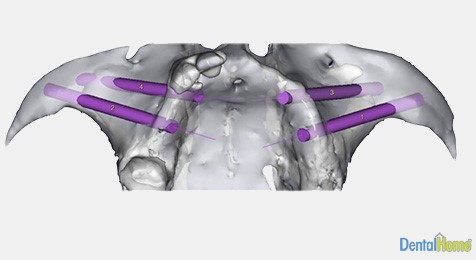

Implante dental cigomatico

En los casos en que se ha perdido severamente el hueso en el maxilar superior y la colocación de implantes convencionales no es la adecuada, el implante dental cigomático es la mejor opción sin tener que realizar grandes procedimientos de regeneración de hueso que en muchas ocasiones son costosos y dolorosos.

Pose un mayor tamaño al convencional y este van sujeto de un hueso debajo del pómulo, este procedimiento es realizado con anestesia general en un quirófano.